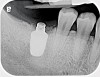

Fig 3. Fractured abutment screw.

Figure 3

Fig 6. Radiograph following crown fracture.

Figure 6